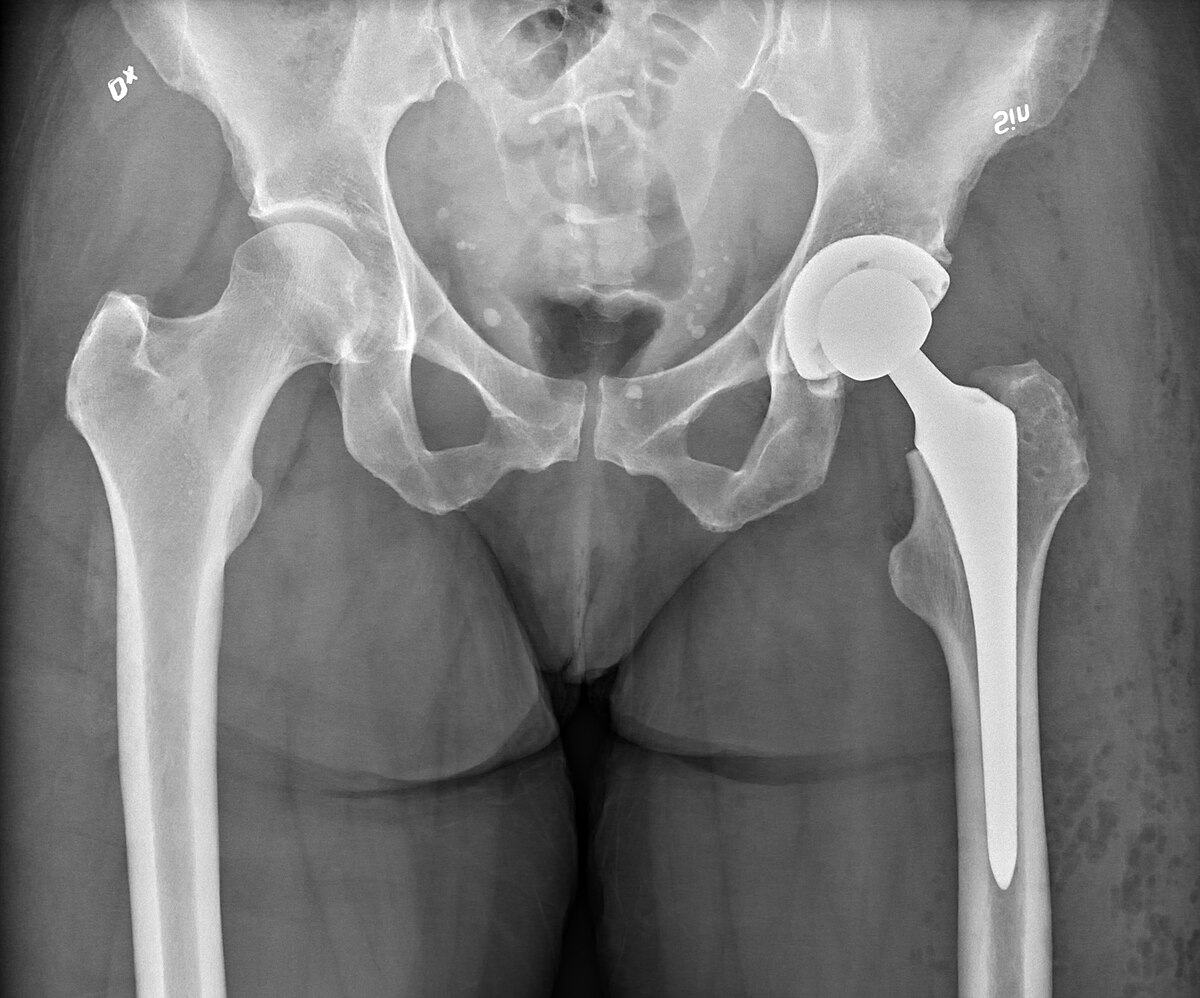

The Orthopedics Department at KGH Hospital specializes in the diagnosis, treatment, and rehabilitation of bone, joint, and musculoskeletal disorders. Our expert orthopedic surgeons manage conditions ranging from fractures, arthritis, and spine problems to joint replacements and sports injuries—using both surgical and non-surgical approaches for optimal recovery.

Joint Replacement & Fracture Management